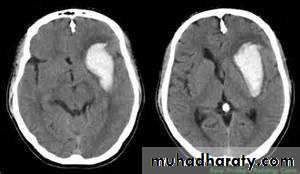

Significant volume of intraventricular blood is a poor prognostic indicator.

The presence of hydrocephalus is associated with a poor outcome.

Non contrast CT followed by CT angiography (CTA) of the brain can rule out SAH with greater than 99% sensitivity.